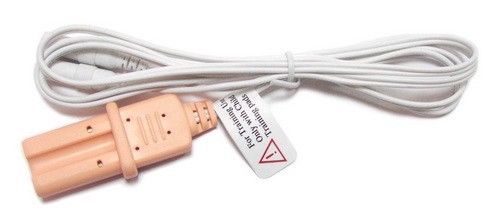

| Model | AED Training Electrode Cable | ||

| MPN | XFT-W120A Electrode Cable Wire | ||

| Be suitable for | XFT-120C+, XFT-120C AED Trainer |